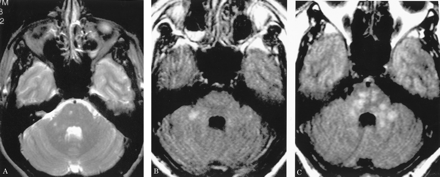

多病灶的幕上的白质病变,包括胼胝体(图1),在所有27个病人,有频繁的参与小脑,中间小脑总花梗,和脑干图1,表)。病变众多,往往是小(3 - 7毫米)但有些小病变成为支流和一些大的(> 7毫米)。19病人实质增强,当明显,导致大脑的粟粒状的外观(图2)。胼胝体的损伤通常是小的,并且涉及中央与周边的相对保留纤维;增强是变量。急性胼胝体的病变(图3)中观察到的活动脑病取而代之的是一个“充满”/穿孔先生出现在后续所有27例(图4),可能代表microinfarctions,没有出现在其他地方。胼胝体,最好在薄片(3毫米厚)矢状T1或T2矢状/质子密度加权图像,由一系列小(3毫米)中央孔相隔7毫米矢状T1和T2矢状/质子密度图像。这些扩展在整个长度的胼胝体。当急性(“雪球”)(见大图3)胼胝体的病变,慢性残余孔较大,尤其是在压部。线性缺陷有时看到的,可能反映microinfarction间接辐射在胼胝体轴突。中央孔(见图4)被认为是由于横向辐射的胼胝体轴突的微型心肌梗塞的可能性。

有深的灰色基底节和丘脑病变19病人(参见表),通常体现在T2信号强度增加,质子密度,和天赋的图像。大病变类似“巨大陷窝”43并建议纹状体外动脉增的广泛参与。三个这样的病人显示这些病变显著增强,伴随着leptomeningeal增强。实质增强(见图2)有关的大脑区域,偶尔与leptomeningeal增强(见相关表)。串行扫描被执行,增强可能是更常见。脑病减弱和病人开始恢复,只有残余病灶中央(见胼胝体的洞图4)和一些白质病变。在两个病人,增加信号强度变化在胼胝体伴随着中央胼胝体的洞在最初的MRI检查。更严重影响病人、脑和小脑萎缩随之而来。在两个这样的实例,胼胝体越来越萎缩,前面提到的胼胝体的洞几乎消失了。